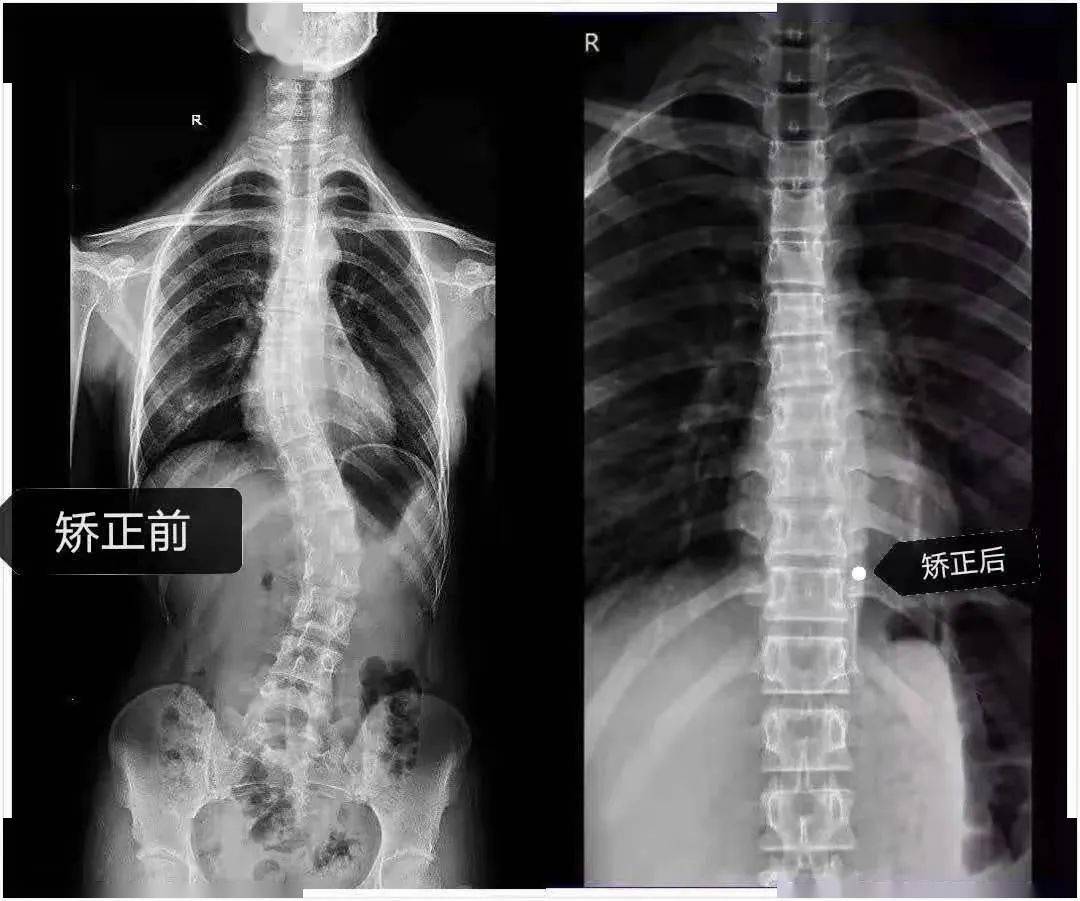

妙龄少女脊柱侧弯,妙手神医巧手扶正

图片尺寸1080x912